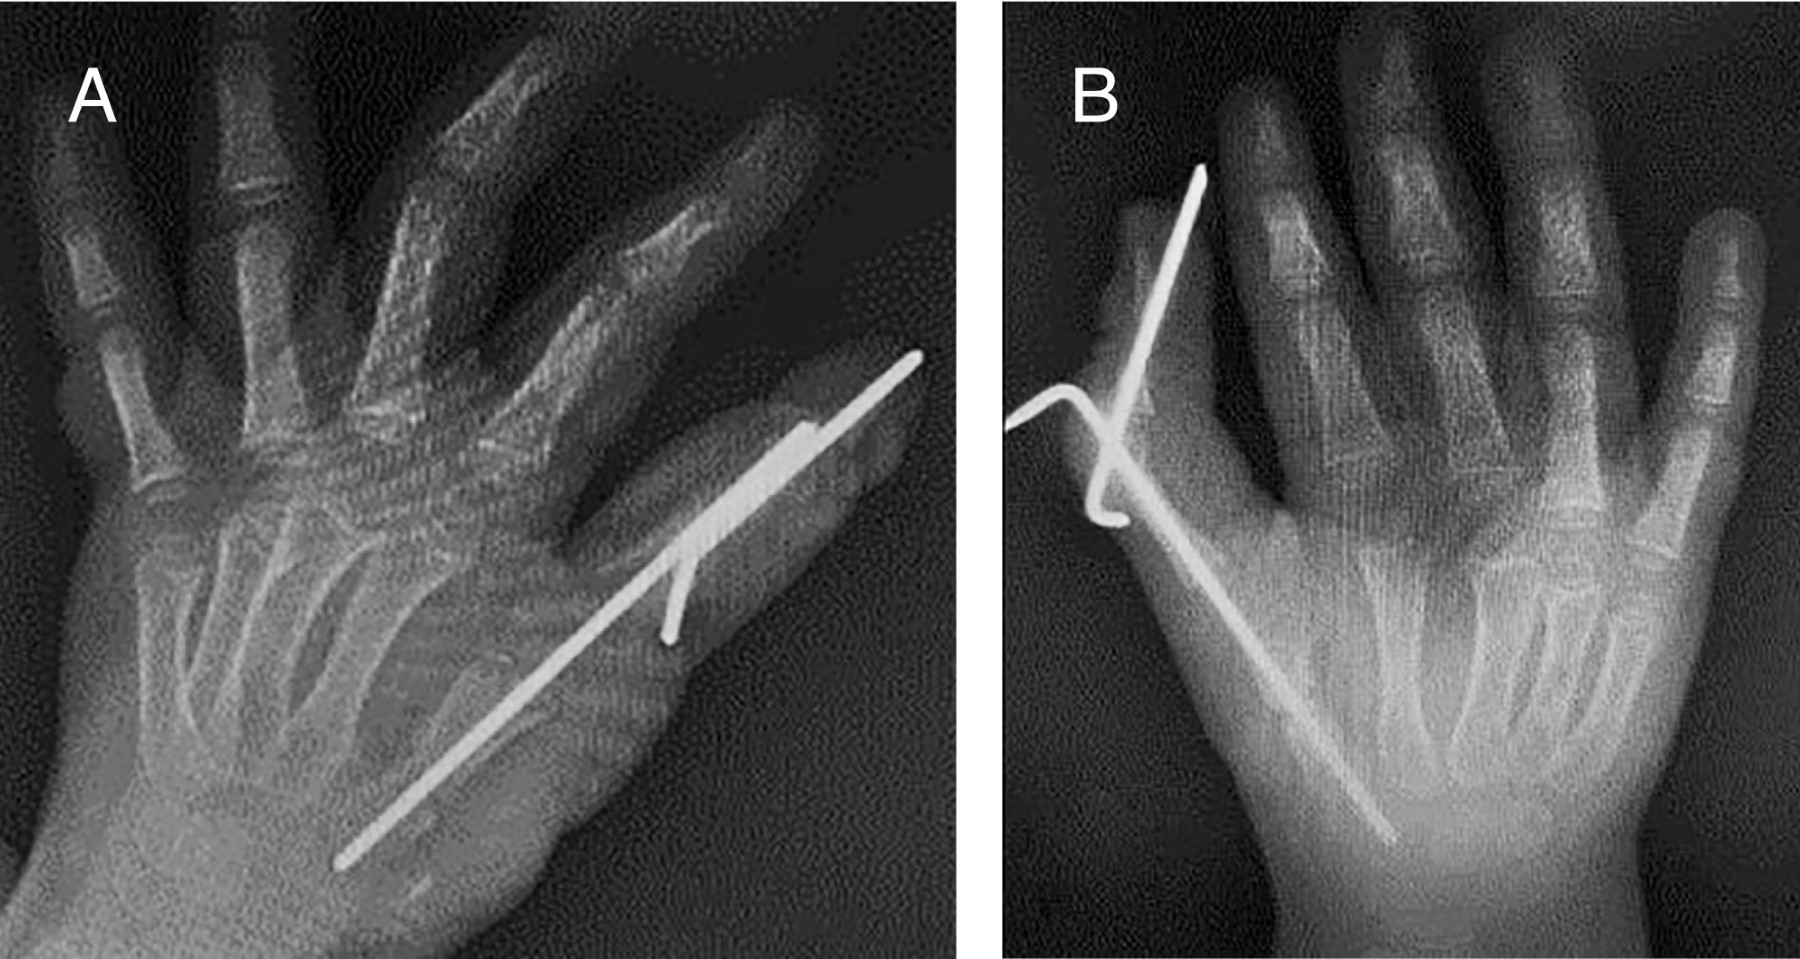

Es llevada a consulta de ortopedia pediátrica debido a presentar un pulgar trifalángico duplicado bilateral así como sindactilia de cuarto y quinto dedo de mano izquierda. En la exploración física inicial, la paciente presenta en ambas manos pulgares supernumerarios, ambos pulgares de longitud anormal, que sobrepasan la articulación interfalángica proximal del dedo índice, pulgar del lado radial sin flexo-extensión, pulgar radial y cubital bilateral con oposición inadecuada, además en mano izquierda presencia de sindactilia de anular y meñique. Radiografía dorso-palmar mano bilateral: donde se observa la presencia de una polidactilia radial, con metacarpo supernumerario y tres falanges. Mano derecha: donde se observa la presencia de un dedo pulgar supernumerario, dependiente de la primera articulación metacarpofalángica, con presencia de pulgar trifalángico, con falange adicional completa (Figura 1). Se ingresa a cargo del servicio de ortopedia pediátrica, para una resección de pulgar radial, la cual se realiza mediante la siguiente técnica quirúrgica: paciente bajo anestesia regional, se realiza una incisión dorsal en el espació entre el pulgar cubital y el dedo índice, además de una incisión a través de las articulaciones metacarpofalángicas, se procede a realizar una resección de la porción proximal del pulgar radial, mediante microsierra, posteriormente se realiza una osteotomía en metacarpiano de pulgar radial a nivel proximal, realizando una resección de todas las estructuras distales a dicho dedo, se realiza reducción y reconstrucción de metacarpos según la técnica de on top plasty y se fija con clavillos Kirschner de 1.2 mm, después se realiza la transferencia de abductor pollicis longus, flexor pollicis brevis y oponente del pulgar, se cierran heridas con sutura absorbible, se realiza mismo procedimiento en ambas manos.

Se mantiene con inmovilización tipo corbata durante cuatro semanas, posterior a esto se retira y se solicitan radiografías de control dorso-palmar y oblicuas de ambas manos observando datos de consolidación ósea grado II de Montoya a nivel de diáfisis media de primeros metacarpianos de ambos dedos (Figura 2).